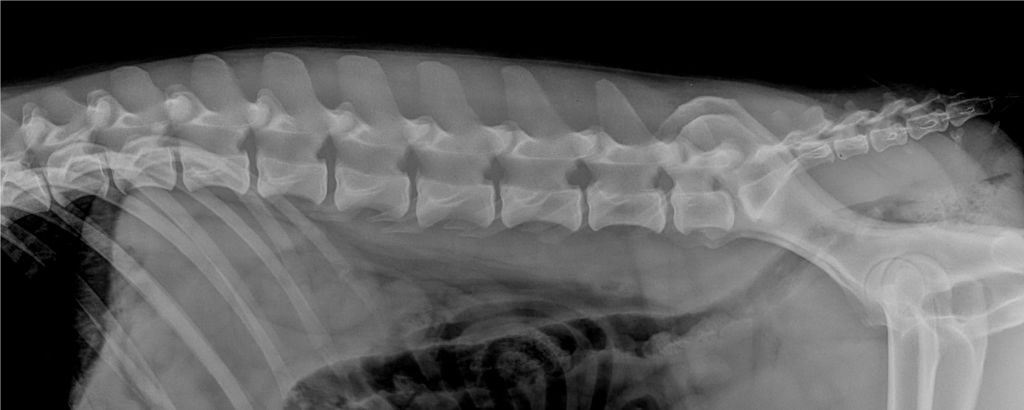

Adn : ADNC Dysplasie des hanches, lecteur français : BC Dysplasie lecteur espagnol : A Indemne de dysplasie renale par échographie : Rdo Indemne de sténoses : Aso pso Spondylose : 0 |